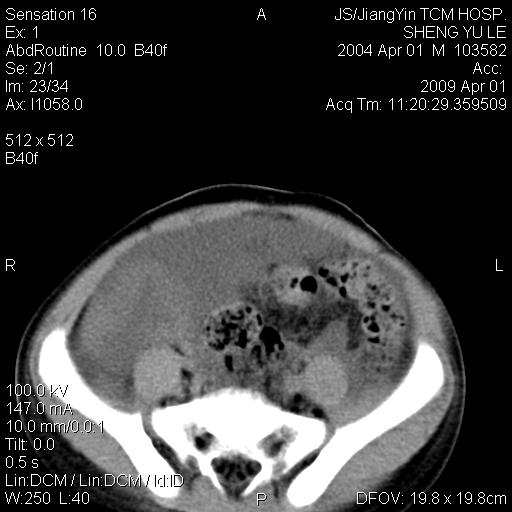

m,5岁。尿痛尿频数天。既往无病史。ct平扫腹盆腔积液。膀胱壁明显增厚。另可见心包增厚。wbc5万,骨髓穿等结果。请指教。

膀胱影像表现结合临床应该是急性膀胱炎症,但为什么有腹水呢?双肾输尿管无扩张,泌尿系压力应该不大不至于引起尿外渗,应该是腹膜感染引起的,但楼主没有提及相关症状,腹膜及膀胱结核?患者白细胞5万(结核不至于这么高啊),脾脏增大,是不是有白血病?进一步检查。。

综合观察分析考虑恶性病变

腹水,膀胱壁增厚,wbc5万,结合临床,支持感染性疾病---感染性腹膜炎、腹水,急性膀胱炎,败血症。期待结果。